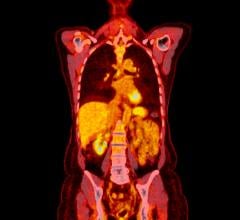

June 15, 2022 — Current guidelines used to plan salvage radiation treatments in patients with local recurrence of prostate cancer should be updated to take into consideration information derived from novel imaging modalities, such as PSMA PET, according to research presented at the Society of Nuclear Medicine and Molecular Imaging 2022 Annual Meeting. The study showed that PSMA PET was effective in identifying recurrences that fell partially or fully outside of the clinical target volume as determined by current guidelines. This suggests that PSMA PET can be an invaluable tool for therapy planning.

After a biochemical recurrence of prostate cancer, salvage radiation therapy can be a curative approach. This therapy conducted following contouring guidelines based on expert consensus, such as the Radiation Therapy Oncology Group (RTOG) guidelines. In today’s era of precision medicine, study authors sought to determine if PSMA PET imaging could provide more detailed data on patterns of recurrence to inform therapy planning.

Prostate cancer patients who experienced biochemical recurrence after radical prostatectomy were included in the analysis if their PSMA PET/CT imaging showed recurrence in the prostate bed. To analyze the patterns of recurrence, two nuclear medicine physicians documented the areas of recurrence on the PSMA PET/CT, and four radiation oncologists (masked to the PSMA PET/CT findings) delineated the clinical target volume using RTOG guidelines on the CT images of the PET/CT. PSMA recurrence locations were then compared to the RTOG-based clinical target volumes.